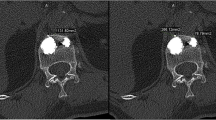

Each FSU was submitted to a computed tomography (CT) scan before and after vertebral fracture. To obtain the volume of vertebral bodies, a dedicated three-dimensional (3D) model was aligned with the vertebral body in the CT image [25]. BMD was measured with dual-energy X-ray absorptiometry. Osteoporosis was defined as 2.5 standard deviations below the mean of a young healthy reference population of the same gender and corresponded to a BMD <0.75 g/m2.

Each FSU was secured in two cups of dental plaster (type IV super hard, Heraeus) and loaded in a computer-controlled hydraulic testing machine (Zwick Roell). Each FSU was positioned in 2° of flexion to simulate a forward stooped posture. The FSU was then compressed at a speed of 200 N/s until one of the vertebral bodies fractured. The yield point was identified by the first nonlinear deformation in a real-time load-deformation graph and the load at yield point was indicated as the yield strength. The fracture was confirmed by a CT scan.

After fracture, vertebroplasty was done using Jamshidi needles (11G) introduced bipedicularly taking special care not to injure the pedicle wall. High-viscosity bone cement polymethylmethacrylate (PMMA, Confidence Spinal Cement System®, DePuy Spine, Raynham, MA, USA) was used to provide better control of cement expansion. Bone cement was injected in increments of 5 % of predetermined fractured vertebral volume to a final injected volume of 20 % of fractured vertebral body volume. The fractured vertebrae were filled in the following way: first bone cement of 5 % of fractured vertebral body volume was injected through one pedicle and the second 5 % (combined 10 %) via the other pedicle. The manoeuvre was repeated for the third (combined 15 %) and fourth (combined 20 % of fractured vertebral volume) injections. Placement of needles and injection of bone cement was monitored closely using alternatively sagittal, frontal and axial plane radiography to show that the needle tips were in the anterolateral part (for the first and second injections) and posterolateral part of the vertebral body (third and fourth injections) as far as possible from lateral borders of vertebrae and vertebral endplates (Fig. 1). Leakage was quantified by collecting the fragments of cement that had leaked and measuring their volume by immersing them in a preset volume of water.

Cement leakage was detected in 5/52 injections (three times during the first injection, once in the third and once in the fourth injection) in three vertebrae on an average of 0.07 ± 0.03 ml per fill. X-ray images showed cement placement adjacent to the vertebral endplate in 10/52 injections (four after the first and two after the second, third and fourth injections). There was no significant difference in compressive stiffness P = 0.96 and IDP P = 0.23 between the group with cement placement adjacent to endplates compared to the group where cement was nonadjacent to the vertebral endplate.